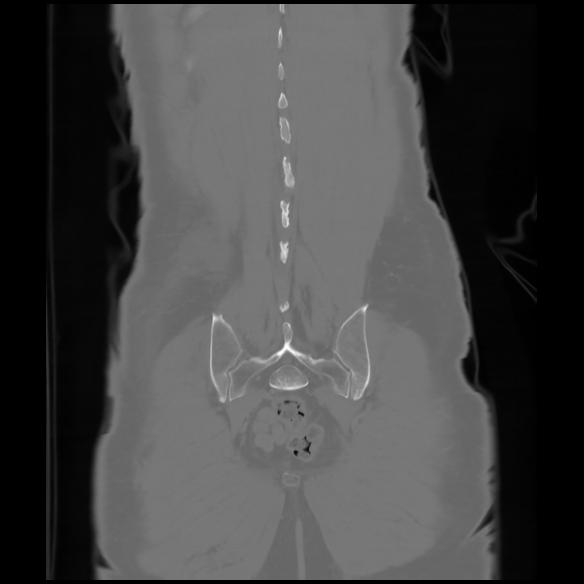

6 CUERPO,CE,Coronal,3.000,CUERPO,Coronal,